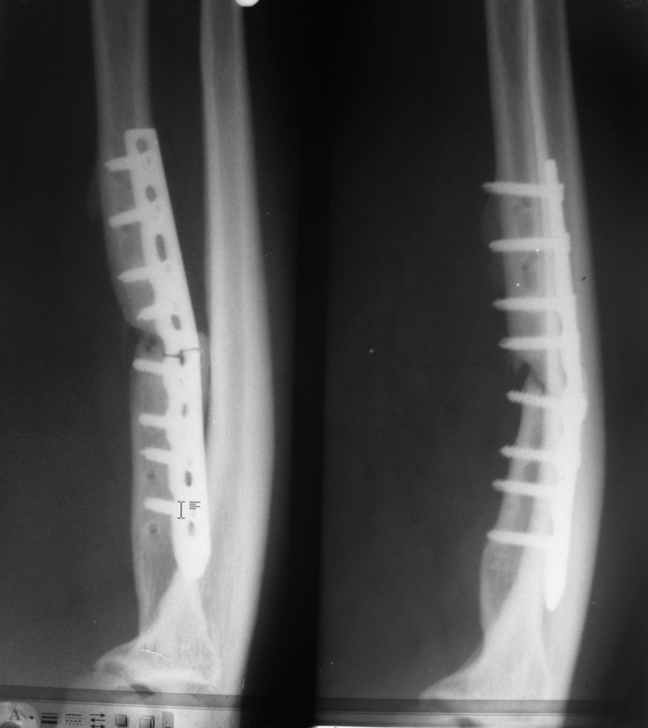

И так, пластину убрали. Далее пластика. В данном случае это именно костная пластика, как своего рода идеал стимуляции костеоброзования с целью минимизации рисков (третья операция, не забываем). Конечно, здесь нет необходимости использовать блоки, тк значимой потери кости нет, к тому же блоки с большей прытью лизируются иногда. Я бы сделал широкую декортикацию (см два на каждом из отломков) и под декортиканты утрамбовал бы аутоспонгиозу, взятую из крыла подвздошной кости шарожкой для обработки вертлужной впадины минимального диаметра. Возможно, спонгиозу смешал бы с крупными или среднего размера гранулами бетта-3 кальций фосфата или иного замениля кости с остеокондуктивными свойствами. Пластина - 3,5 мм, наверое, лучше блокированная, несмотря на неплохое качество кости. Количество отверстий - 10 - 11. На прокимальном отломке пластина лежит на этом же уровне, не выше, дабы избежать неприятного контакта с глубокой ветвью лучевого нерва. А это значит, что удастся установить только три самых прокимальных винта, дабы дистальнее создать мост. Поэтому, если вдруг какой либо из винтов не будет оптимально притягивать пластину к кости, допустим одно из предыдущих отверстий здесь было, надо иметь возможность блокирования. Дистально - 3 или 4 самых дистальных винта, больше - нет смысла и даже вредно. Тогда и мост для эластичности будет достаточным. Поверхность кости для пластины выбираем такую, что бы при минимальном моделировании максимально исправить деформацию. Иммобилизация не нужна. Особой физкультуры не нужно - за искючением, пожалуй, мячика-эспандера. Так же вплоть до сращения придётся избегать отжиманий на кулаках, в чём очевидный недостаток предложенного плана. Но надо потерпеть, ничего не поделаешь... В приложенном файле что-то немного похожее. Ложный сустав локтевой кости. Декортикация плюс керамика без аутокости. Не всё идеально, конечно, но функция полная и результат достигнут. С уважением, Андрей

ЛС.ppt

1464KB (1499648 bytes)

Оперировал сегодня. Благодарю всех за советы, считаю, что ни один из них не пропал даром. на операции- полное отсутствие каких-либо намёков на костную мозоль, сломанная пластина удалена без проблемм, выполнена декортикация, освежение концов отломков, вскрытие каналов, костная пластика с подвздошной кости, пластина LCP на 10 отверстий по 3 винта с каждой стороны. По всей видимости на первых операциях было весьма сильно нарушено кровоснабжение кости. Опыт применения аппаратов внешней фиксации на предплечье у меня достаточно невелик, в основном ограничен временной фиксацией открытых переломов до заживления ран, рисковать не стал. Пластика по Хахутову обсуждалась, но показалась сложней и травматичней. В целом, операцией доволен, а отдалённый результат...буду ждать. Ещё раз всем спасибо. Кирилл